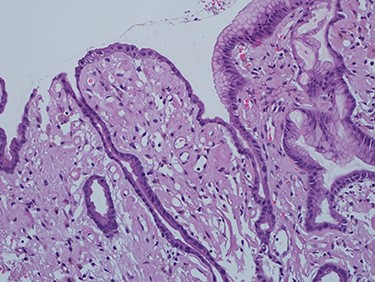

As work up for his abdominal pain and anemia he underwent gastroscopy on 29 October 2020 that revealed congested and nodular gastric mucosa (mass-like) and at lesser extend in the first and second part of duodenum (Figs 1 and 2). Biopsies were taken from the gastric lesion and duodenum. Histopathological findings from gastric mass and duodenum showed marked stromal hyalinosis, which appeared as a cellular pink material on H&E stain (Figs 3 and 5). Congo red stain (amyloid stain) showed apple green birefringence under polarized light on both gastric and duodenal biopsies (Figs 4 and 6).

High power of gastric biopsy showing prominent stromal hyalinosis, (H&E x20).